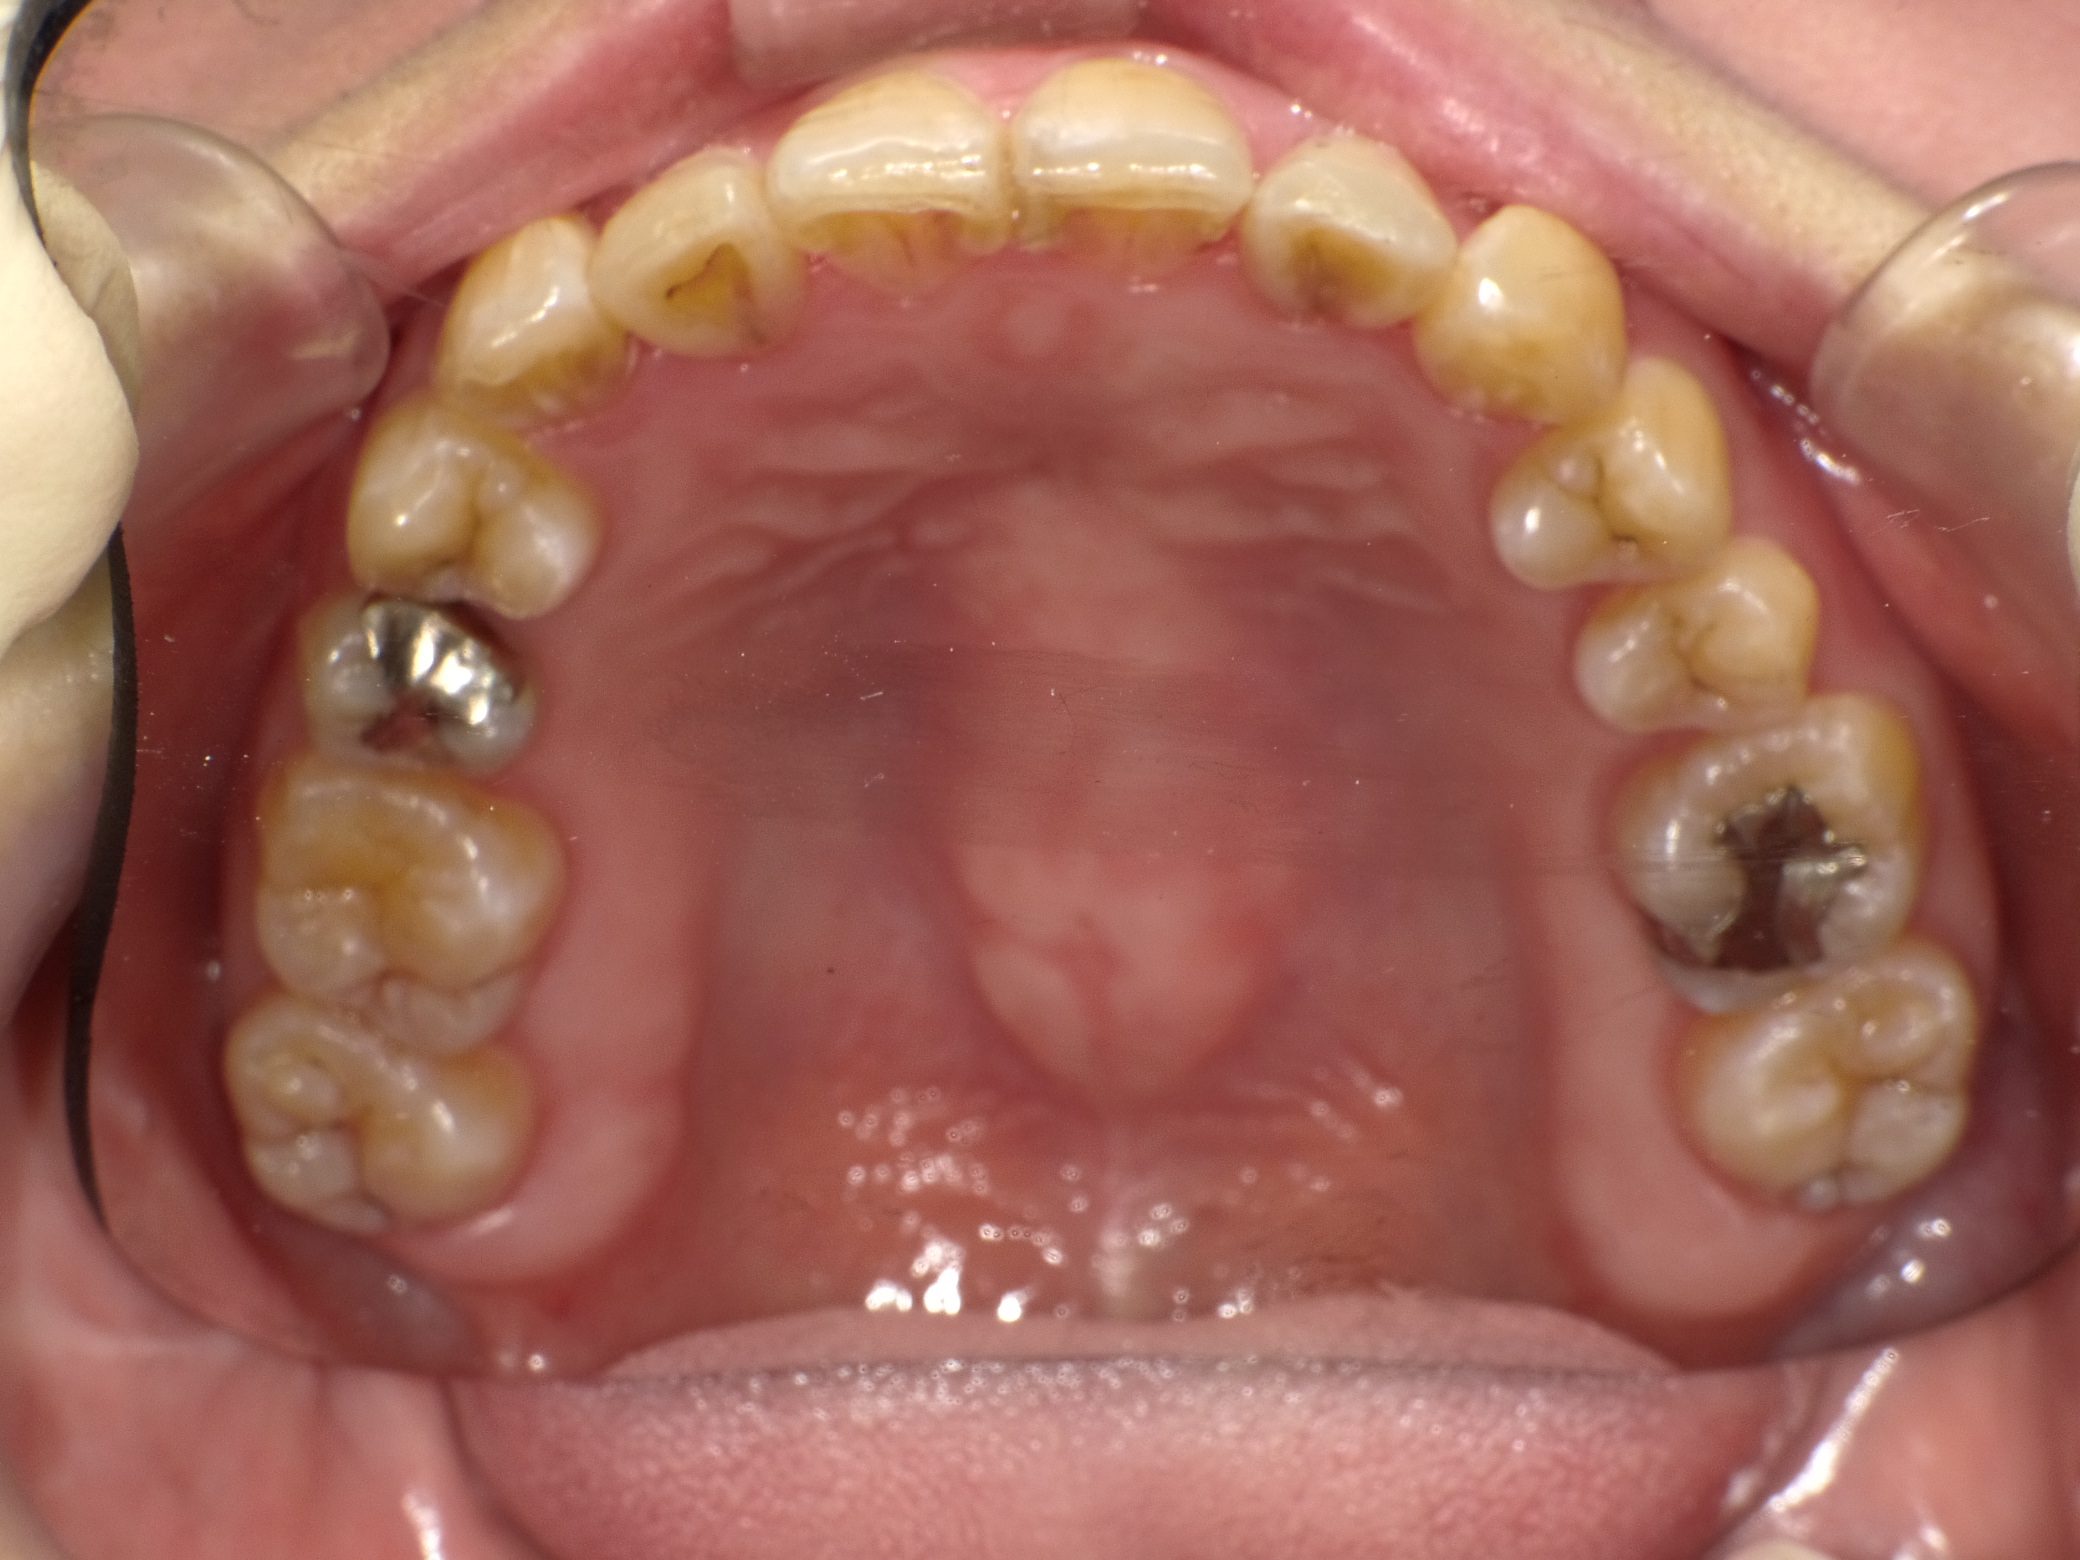

Before

After

【社会人】インビザラインフル 反対咬合(受け口)を改善 下顎前歯1本抜歯

全く装置の浮きがなくしっかり使ってくれたので2年で終了しました。

10年前の治療ですが、今もしっかり後戻りせずに歯並びを保たれています。